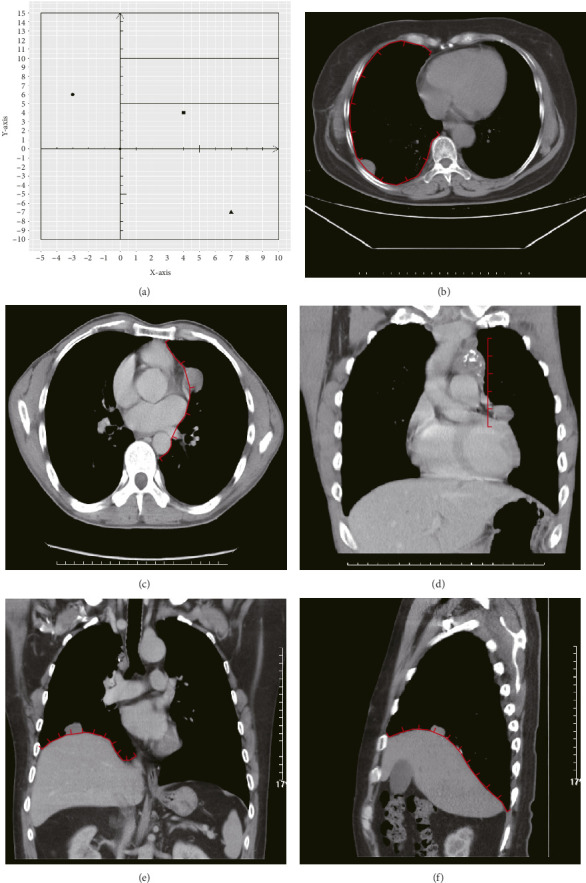

Background: Thymoma is a common malignancy with low incidence, and pleural metastases are common pattern of recurrence. It is necessary that the spatial location of pleural metastatic lesions be analyzed. This study aimed to analyze the spatial distribution patterns of pleural dissemination in patients with thymoma and evaluate the variables that influence the survival of pleural metastasis in this population. Methods: This retrospective study investigated hospital admissions of patients diagnosed with pleural metastasis from thymoma. The spatial distribution pattern and visualization of the pleural metastases were analyzed after establishing a coordinate system. We further analyzed the survival and influencing factors in patients with pleural metastases from thymoma. Results: The analysis included 56 patients with a cumulative count of 365 pleural metastases, with 351 metastases from Zones 1-5 finally included in the analysis. The spatial distribution of the 285 initially diagnosed pleural metastases was significantly concentrated in Zones 3 and 4 near the lateral half of the spine (56.5%), followed by Zone 5 (17.5%). Collectively, these two components accounted for 74.0% (211/285) of all initial metastatic lesions. The survival rates at 5 years for those who underwent surgery versus nonsurgical treatment were 68.3% and 37.1%, respectively (p=0.015). Univariate Cox regression analysis showed that surgical intervention reduced the risk of death by 61%. Conclusions: The distribution of pleural metastatic lesions exhibited a nonuniform pattern, primarily concentrated on the spinal aspect below the aortic arch of the costal pleura and the spinal aspect of the diaphragmatic pleura.